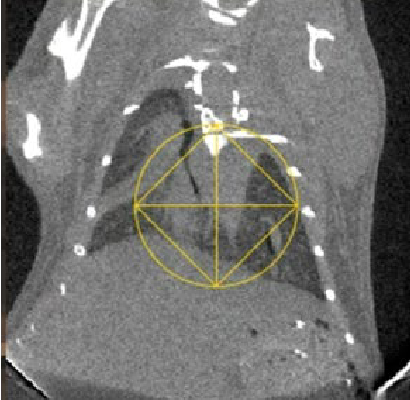

Fig 2. Reconstructed CBCT image of a mouse with lung fibrosis as viewed in the SmART+ software. (Left) Axial, (Center) Sagittal and (Right) Coronal views.